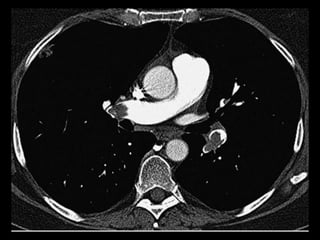

Malformação arteriovenosa(MAV)

MAV congênitas: fístulas vasculares com

comunicação entre a artéria e a veia pulmonar(95%)

ou de uma artéria sistêmica e a veia pulmonar com

by-pass do leito capilar;

Cerca de 50% das MAVs estão associadas com

O diagnóstico costuma ser bem direto pela TC;

TC: o aspecto típico é de uma massa regular,

lobulada, redonda ou oval, ou até o de uma

formação serpenginosa, com menos de 1 cm a

vários cm de tamanho, associada a uma artéria

nutriz visivelmente aumentada e uma veia de

drenagem alargada;

Uma ANGIO-TC geralmente faz o diagnóstico;

Tratamento pode ser realizado com terapia

embólica.

MAV complexa

Malformação arteriovenosa(MAV) TC:o aspecto típico é de uma massa regular, lobulada, redonda ou oval, ou até o de uma formação serpenginosa, com menos de 1 cm a vários cm de tamanho, associada a uma artéria nutriz visivelmente aumentada e uma veia de drenagem alargada; Uma ANGIO-TC geralmente faz o diagnóstico; Tratamento pode ser realizado com terapia embólica.